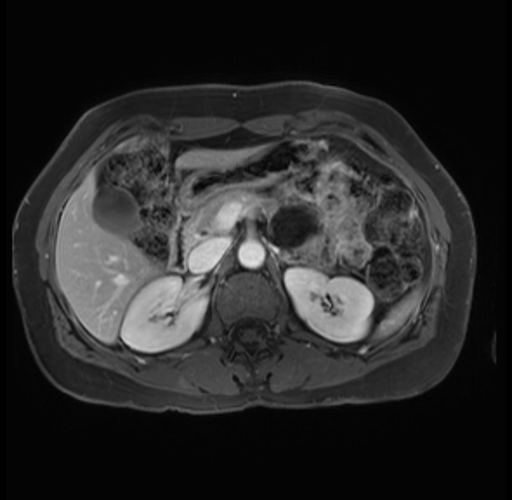

Imaging Analysis

Look through the patient's CT scan to identify any areas of concern for the necessary procedure.

Based on your CT findings, which issue(s) are present and would give reason for "planned slowing down moment(s)" in this case?